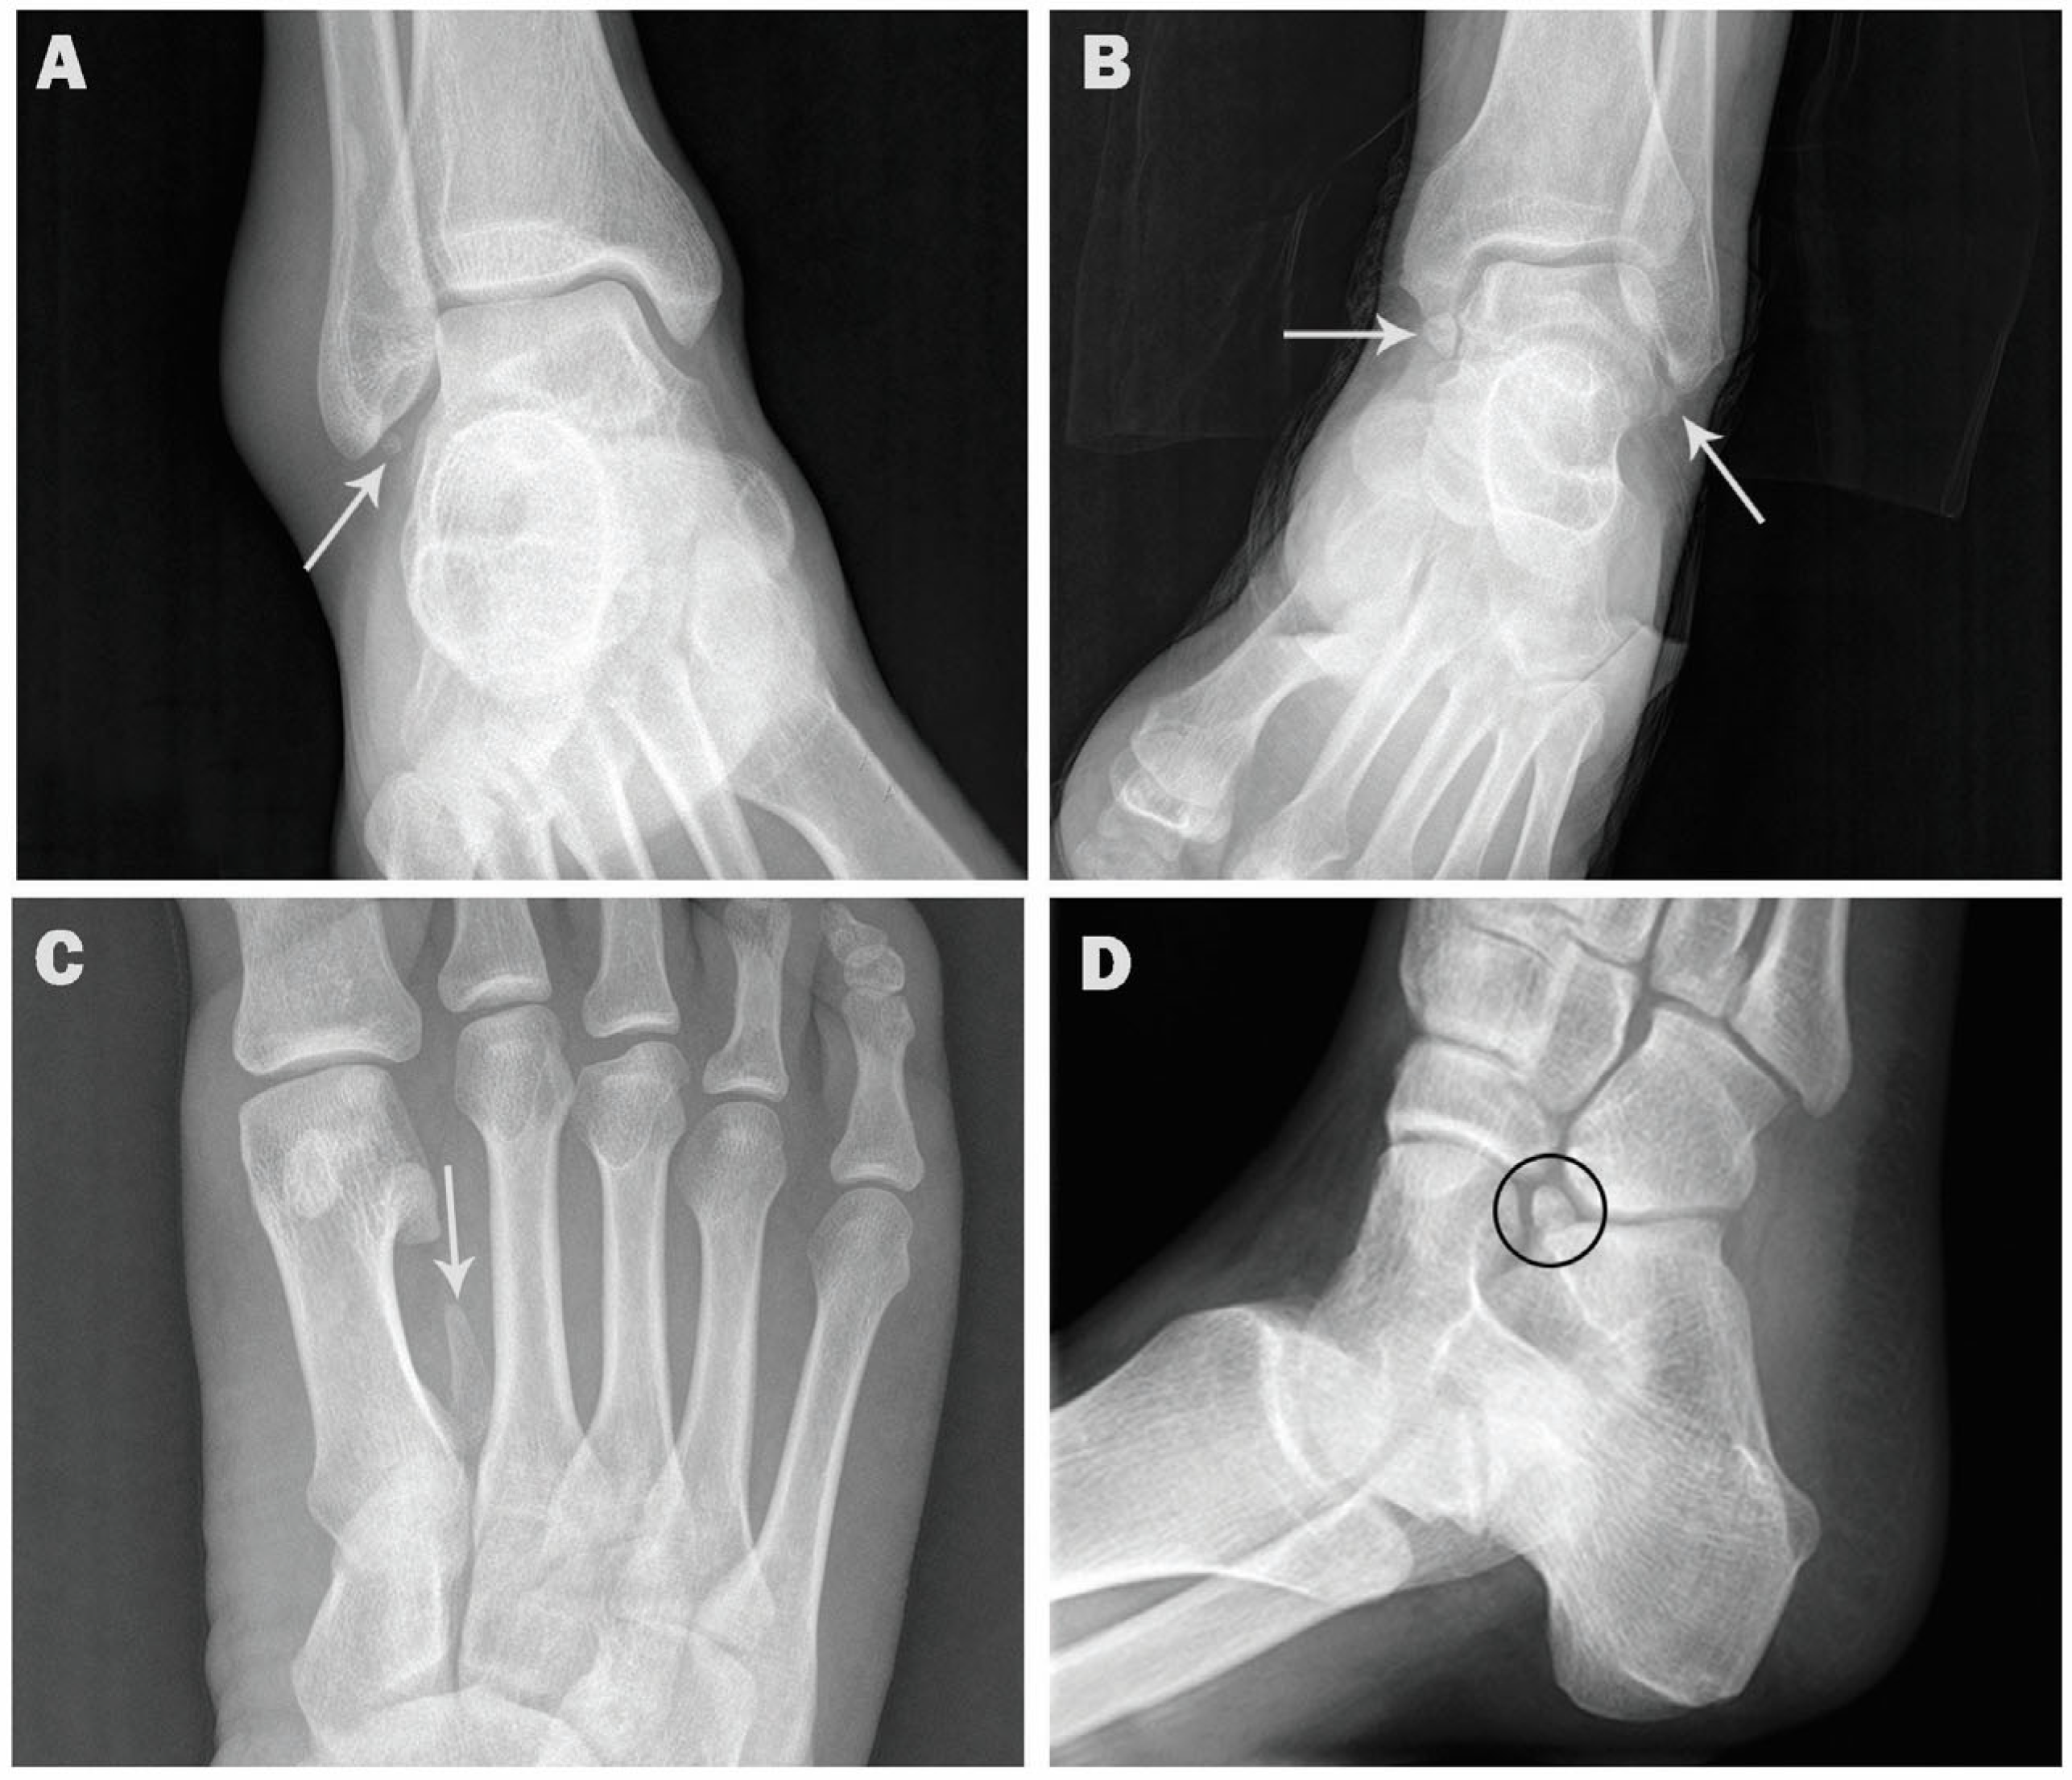

| Os trigonum | 154 (15.4) | 65 (13.0) | 89 (17.8) | 105 (15.6) | 49 (15.0) |

| Accessory navicular | 137 (13.7) | 77 (15.4) | 60 (12.0) | 99 (14.7) | 38 (11.7) |

| Os peroneum | 115 (11.5) | 64 (12.8) | 51 (10.2) | 81 (12.0) | 34 (10.4) |

| Os intermetatarseum | 2 (0.2) | 1 (0.2) | 1 (0.2) | 2 (0.3) | 0 (0) |

| Os vesalianum | 11 (1.1) | 7 (1.4) | 4 (0.8) | 9 (1.3) | 2 (0.6) |

| Os calcaneus secundarius | 3 (0.3) | 2 (0.4) | 1 (0.2) | 2 (0.3) | 1 (0.3) |

| Os supratalare | 3 (0.3) | 2 (0.4) | 1 (0.2) | 1 (0.1) | 2 (0.6) |

| Os subfibulare | 6 (0.6) | 2 (0.4) | 4 (0.8) | 3 (0.4) | 3 (0.9) |

| Os supranaviculare | 7 (0.7) | 6 (1.2) | 1 (0.2) | 4 (0.6) | 3 (0.9) |

| Os infranaviculare | 3 (0.3) | 2 (0.4) | 1 (0.2) | 2 (0.3) | 1 (0.3) |

| Os subtibiale | 1 (0.1) | 1 (0.2) | 0 (0) | 0 (0) | 1 (0.3) |

| Os talotibiale | 4 (0.4) | 3 (0.6) | 1 (0.2) | 2 (0.3) | 2 (0.6) |